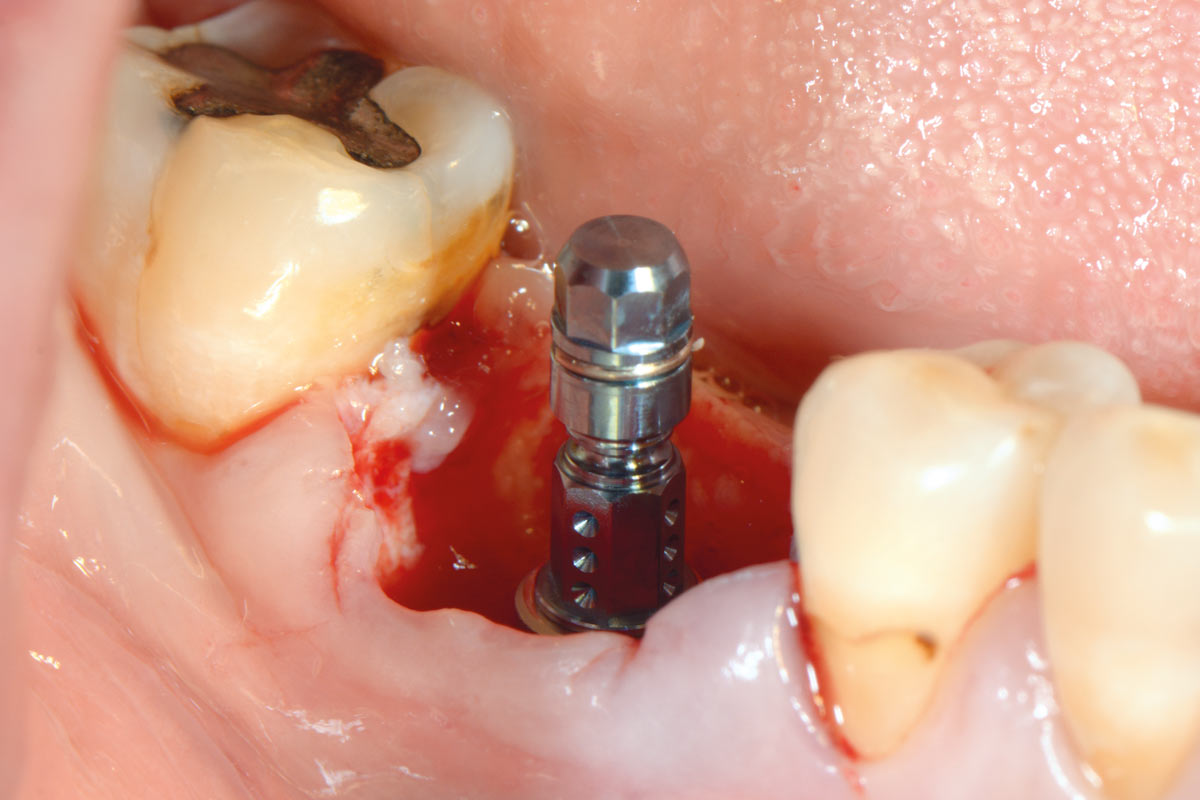

47 years old patient referred by another dentist after suffering a fall while fishing